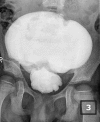

Congenital pouch colon is an anomaly always associated with anorectal malformation, where the colon is replaced by or terminates into a large aperistaltic intestinal pouch. Vertebral anomalies leading to neurogenic bladder are rare associated malformations. The pouch is aperistaltic and thus a poor rectal substitute but this very property makes it ideal for bladder augmentation. We report the first case where the pouch has been used to augment a high-pressure neurogenic bladder.